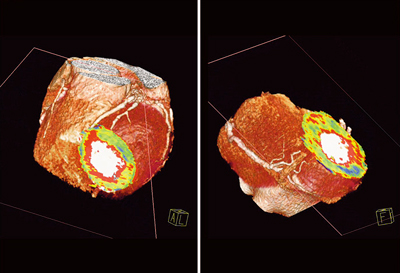

心筋パーフュージョンCTの読影においては,4D Displayにより元画像を視覚的に評価するよりも,定量解析結果であるperfusion mapを評価する方が心筋血流異常を容易にとらえることができる(図7)。当院では,主にperfusion mapで読影し,補助的に4D動画を使用している。

図7 4D Displayとperfusion map(症例2)